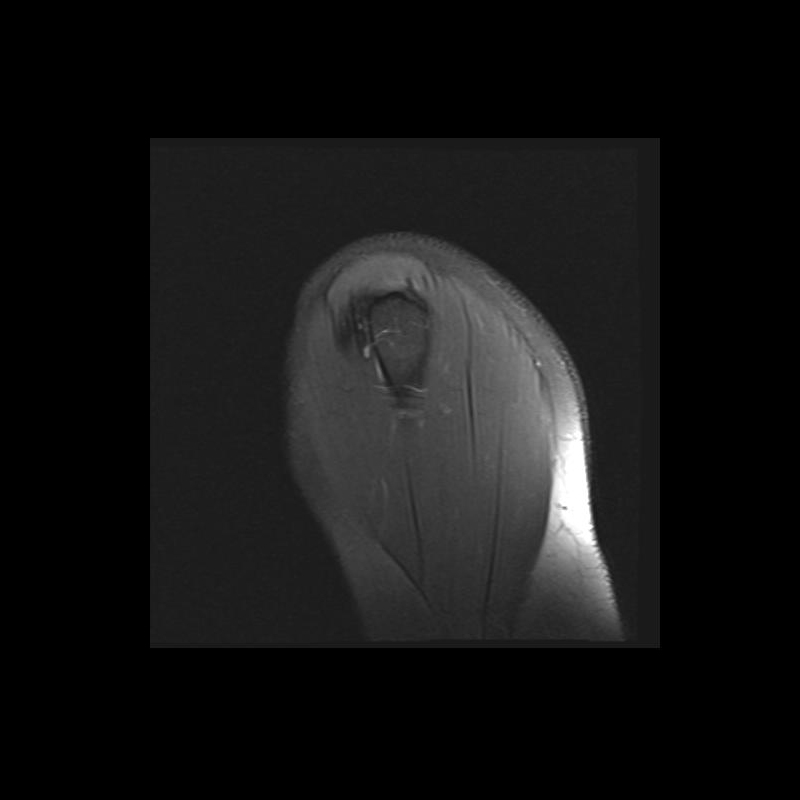

Shoulder MRI Anatomy